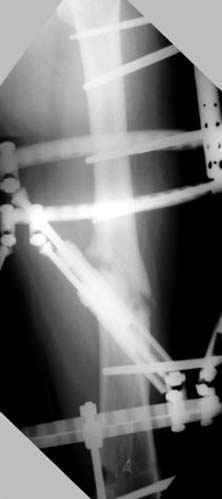

N3 рисунок окончательный снимок, после операции моя рентгенограмма должен выглядеть примерно как эта картина. На N4 снимке клин перед удалением; N5 послеоперации 3 нед.; N6 окончательная рентгенограмма.

пластическая модель; и коррекция бедра аппаратом Илизарова.

хотя даже если бы и инфекция , то nail exchange с рассверливанием канала - вариант дебрайдмента) Я думаю, что последовательность развития событий:

Узкий к-м канал - тонкий гвоздь- усталостный перелом дистальных винтов - развитие нестабильности и как ее результат остеолиз вокруг гвоздя - деформация анатомической оси бедра. Похоже, что я понял почему аппарат, а не новый гвоздь:-)